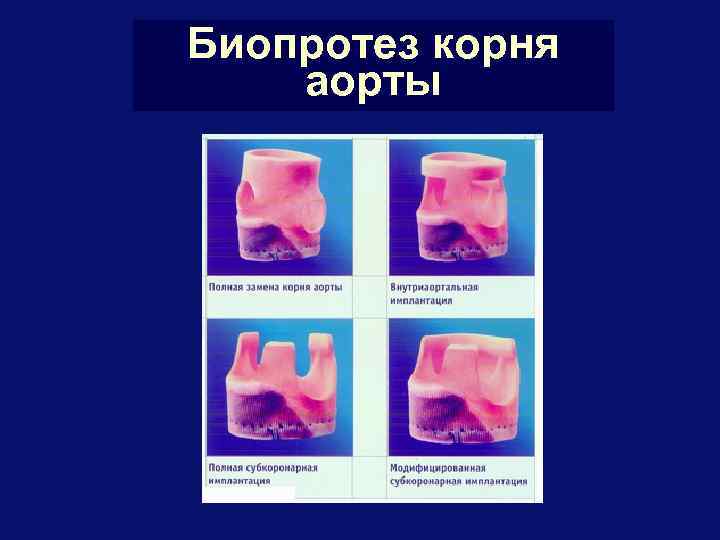

Биопротез корня аорты